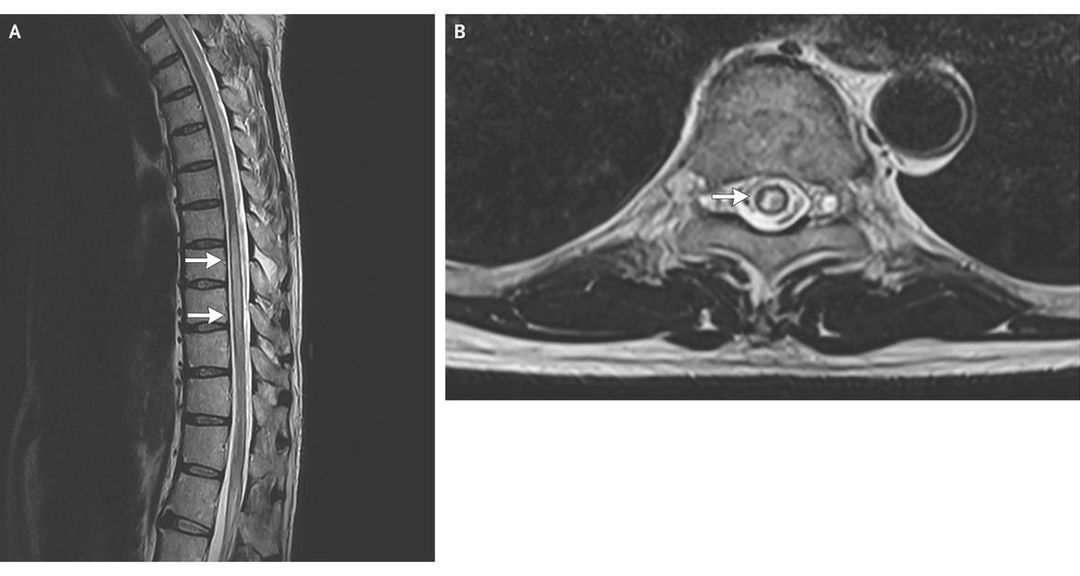

A 59-year-old man presented with a 5-day history of bilateral lower-limb numbness, unsteadiness of gait, and urinary incontinence. On examination, he had bilateral lower-limb weakness (strength, 4/5), with normal tone and deep-tendon reflexes. The plantar reflexes were normal bilaterally. There was a sensory level at T10. Visual evoked responses were delayed on both sides. Absence of the superficial abdominal reflex on the right side (see Video) correlated with the finding of a hyperintense lesion in the spinal cord on T2-weighted magnetic resonance imaging, spanning T7 to T10 (Panel A, arrows), predominantly on the right side (Panel B, arrow). The analysis of the cerebrospinal fluid was normal. A test for anti–aquaporin 4 (NMO-IgG) antibodies was positive. He was given a diagnosis of neuromyelitis optica and treated with intravenous methylprednisolone for 5 days. Azathioprine therapy was also initiated. At 1-month follow-up, his neurologic deficits had resolved completely except for some residual sensory symptoms. The superficial abdominal reflex can be used for localization of lesions in the thoracic spinal cord. It is elicited by gently stroking each of the four quadrants of the anterior abdominal wall. A normal response is a visible contraction of ipsilateral abdominal muscles. This reflex is now considered to be of minor clinical significance owing to the availability of neuroimaging studies and the difficulties in eliciting the reflex in multiparous women and patients who are anxious, elderly, or obese.